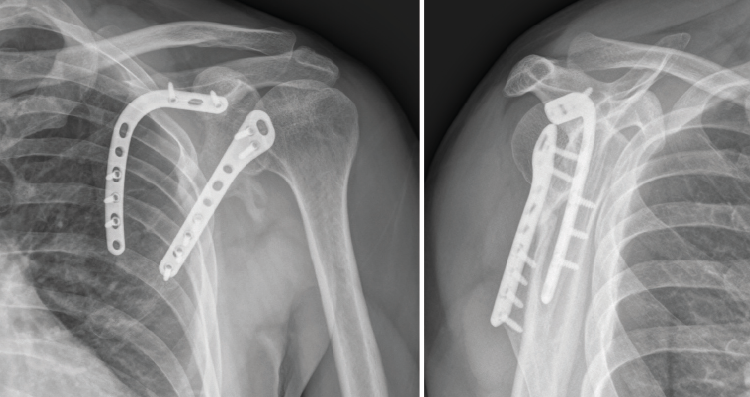

En el control de la cuarta semana postoperatoria se observaron signos de consolidación radiográfica y ausencia de dolor sin medicación analgésica (escala visual analógica = 0). Al final del seguimiento (7 meses tras el tratamiento quirúrgico) el paciente conseguía una movilidad activa consistente en 120° de flexión y de abducción, una rotación interna suficiente para tocar con el pulgar su espalda a nivel de la vértebra T12 y una rotación externa en la que conseguía llevarse la mano a la nuca sin antepulsar el codo. Se evidenció, no obstante, una leve pérdida de fuerza con respecto al hombro contralateral. Tras 112 días de baja laboral desde el día del accidente, el paciente fue reincorporado a su puesto de trabajo laboral sin secuelas reseñables y con el control radiográfico que se muestra en la Figura 11.

Figura 11. Control radiográfico al final del seguimiento (7.º mes postoperatorio).